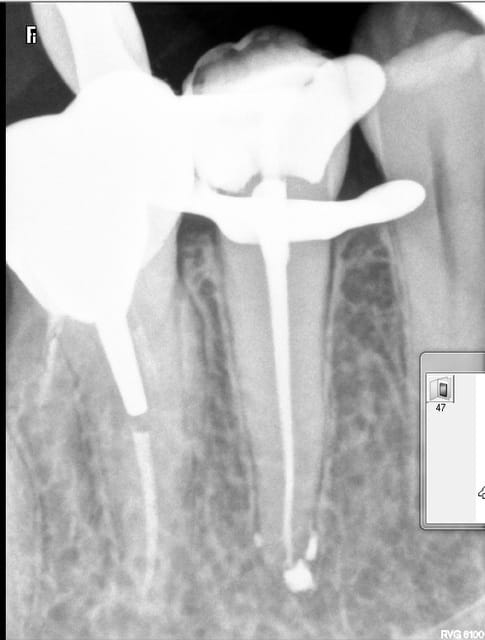

par provoc on s'est amusé à faire une photo

pour répondre à la question avec quoi j'obture : maitre cone et condensation verticale simplement

promis je ne polluerais plus les posts d'endo

cadeau (si je puis me permettre) de fin

mon objectif avait été de dire qu'on pouvait aussi faire simple mais la critique SYSTEMATIQUE me casse les c...

le pire venant de ceux qui n'osent jamais poster bien sur ce n'est pas toi giminy que je pointe

tchao